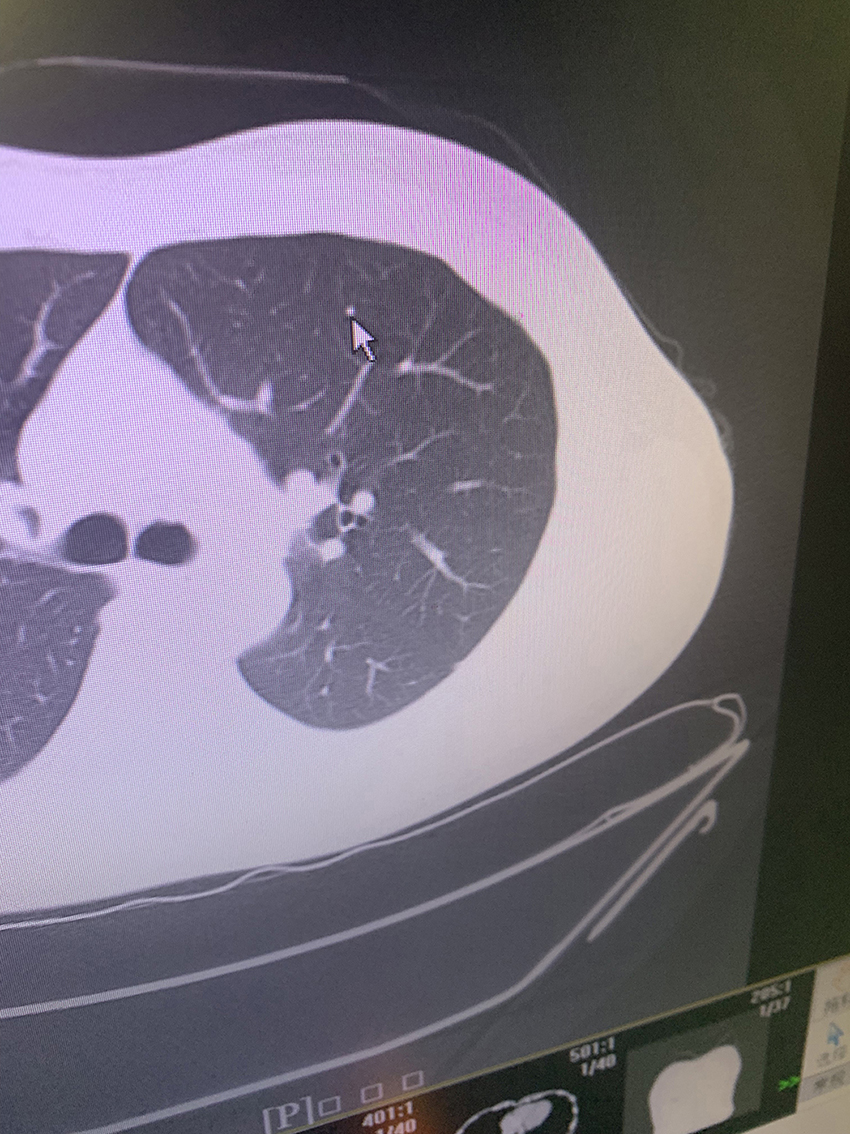

您好戴主任,我10天前体检发现肺数枚小结节,报告上只右肺有,医生看了说左右肺都有让三个月CT复查,报告也没说是实性结节还是磨玻璃,只写边界清,大的直径4MM。我39岁抽烟15年,戒有4年了,这几天心里特紧张,一直想这个事,吃不好,睡不好。在医生电脑上拍了几张照片麻烦戴主任帮看看,感谢!@重庆戴纪刚

实性微结节,良性的,偶尔复查